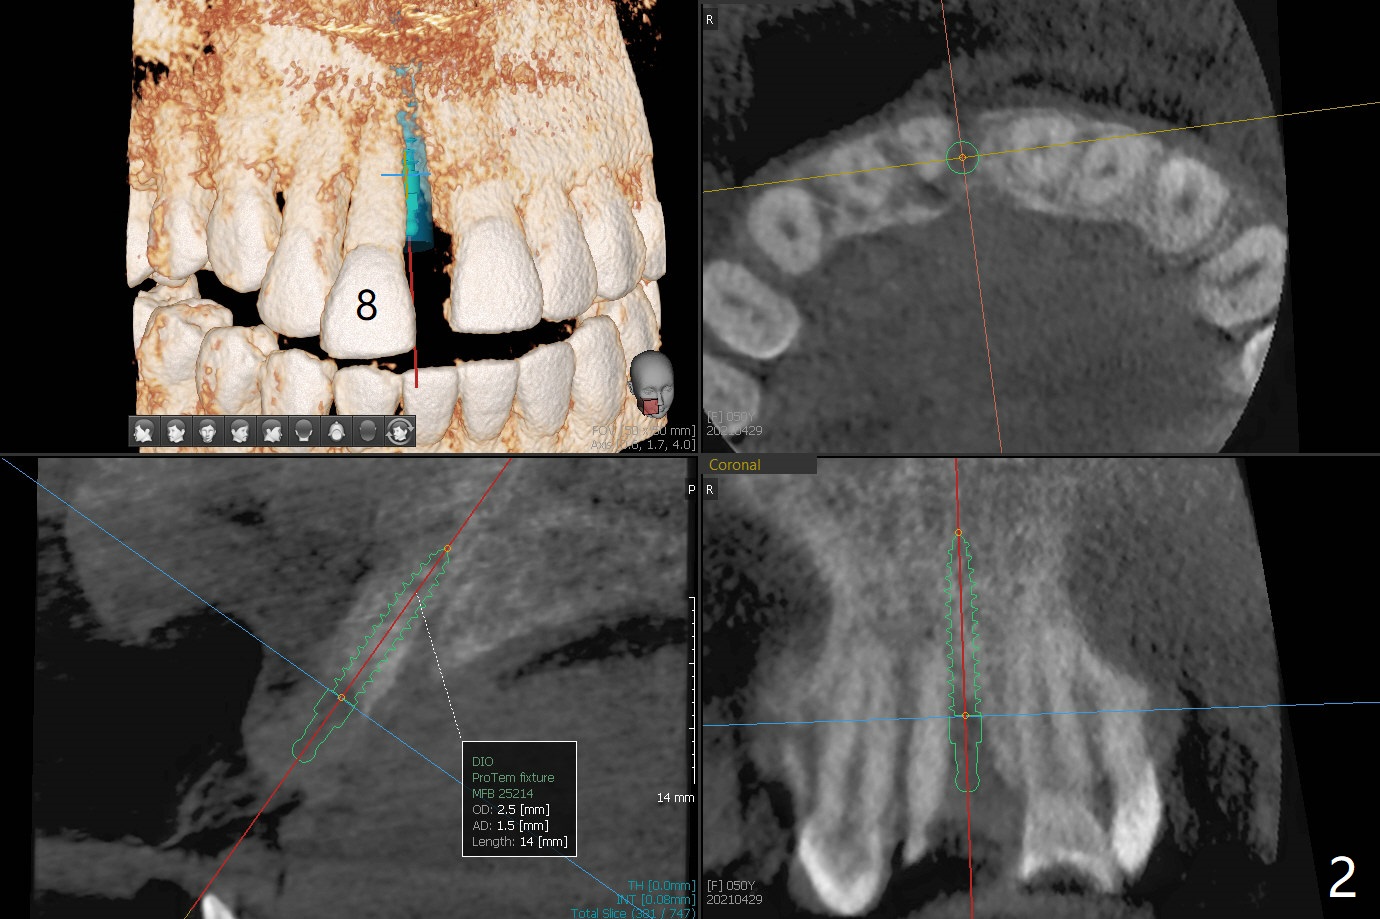

A 50-year-old woman complains of #8 buccodistal shifting (Fig.1,2). Conduct occlusal equilibrium until the affected tooth returns to its normal position. Trim the crown shell of the extracted tooth subgingival to the tooth #9 as a temporary crown (Fig.3,4). The gap between the socket and the tooth shell will be filled with sticky bone and PRF and covered by periodontal or acrylic dressing. The palatal bone loss is also severe (Fig.5); PRF should cover the palatal defect following sticky bone with a hole over the abutment.